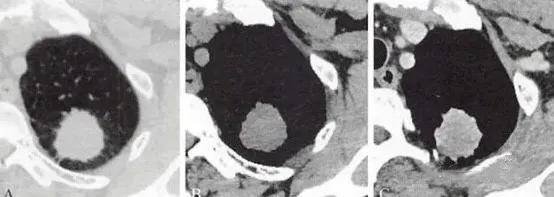

(1)中央型,肿瘤发生在段支气管以上的支气管,亦即发生在叶支气管及段支气管,以鳞状上皮细胞癌和小细胞未分化癌多见。

a. 阻塞性肺气肿;b.阻塞性肺炎:小片状、肺段